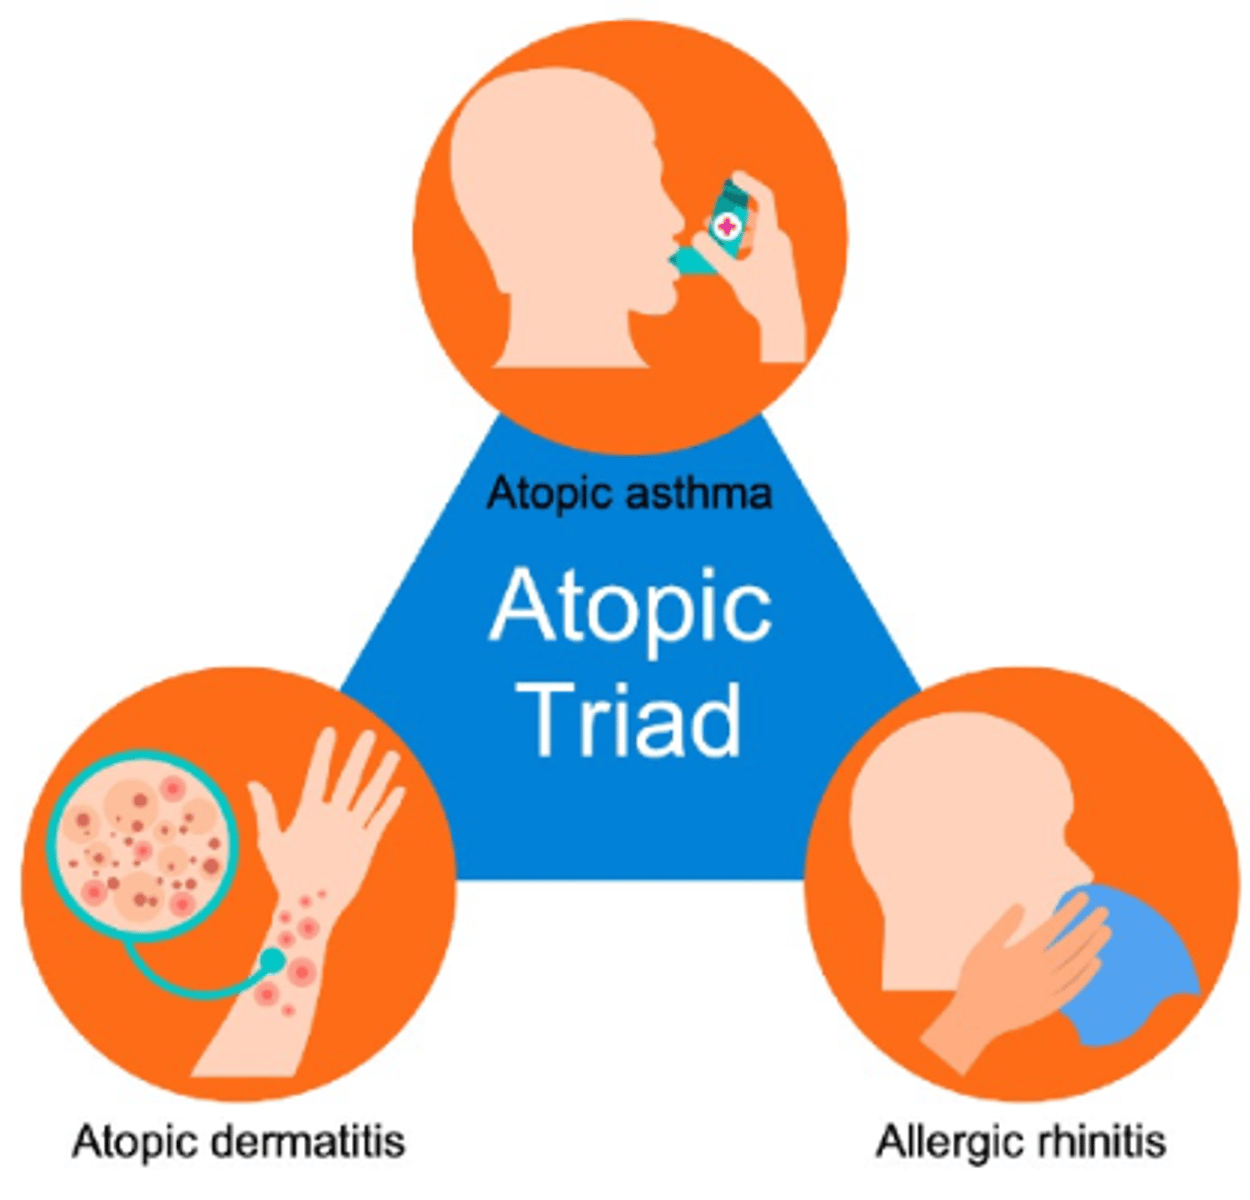

Eczema

Inflammation of the epidermis. Prutis=itchy, no cure

common Triad

Asthma

Hay fever (Allergic rhinitis)

Eczema